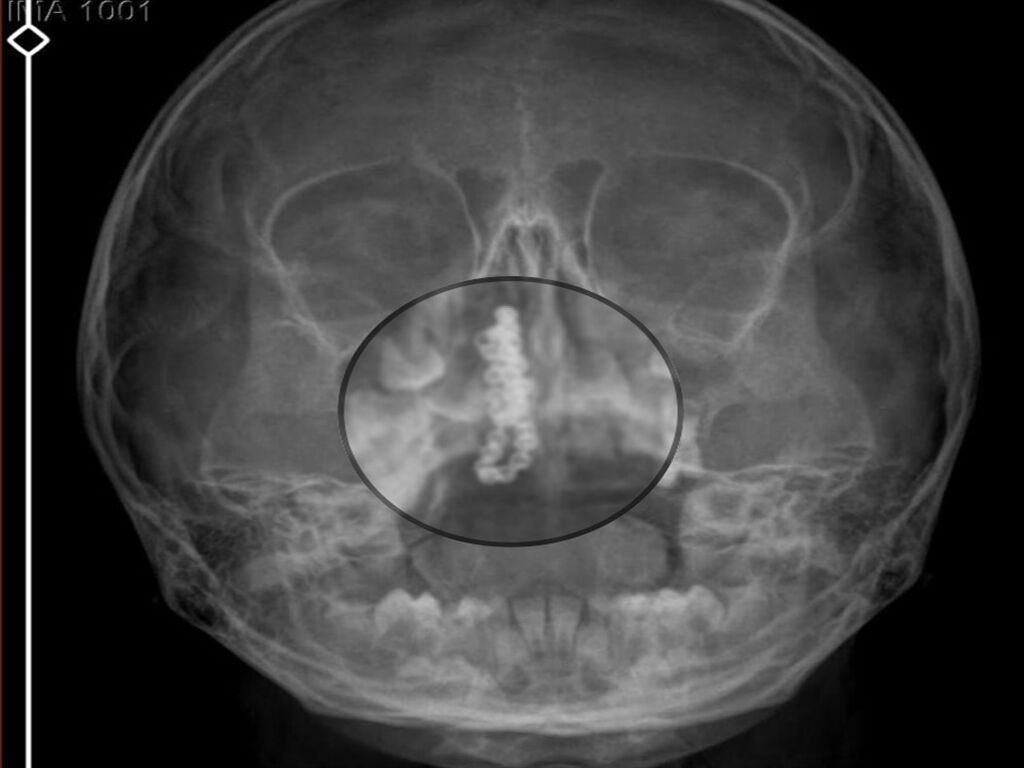

Kentte yaşayan Gökhan-Nalan Tekin çifti, yaklaşık 4 ay önce şiddetli burun kanamasının yanı sıra akıntı şikayetleriyle kızları Polen'i, bir özel hastaneye götürdü. Burada röntgeni çekilip, tetkikleri tamamlanan küçük kıza, iddiaya göre enfeksiyon teşhisi konulup, ilaç verildi. Eve dönen aile, kanama ve akıntının geçmemesi üzerine bu kez Rize Devlet Hastanesi'ne giderek Kulak Burun Boğaz Polikliniği'ne başvurdu. Devlet hastanesindeki doktorun incelemesi ve kapsamlı röntgen çekilmesi sonrası Polen'in burnunda metal cisim olduğu fark edildi. 2 yıldır burunda kaldığı değerlendirilip, küçük top şeklinde tırnak makası zinciri olduğu belirlenen cisim, başarılı ameliyatla çıkarıldı. Bir süre tedavisi sürdürülen Polen, sağlığına kavuşunca taburcu edildi. Özel hastane yetkilileri, konuyla ilgili açıklama yapmazken; aile suç duyurusunda bulunacaklarını söyledi.

Kızının burnundan sürekli siyah renkte akıntı olduğunu anlatan Gökhan Tekin, "Çocuğumun burnundan kanama ile sürekli siyah akıntı geliyordu. Özel hastaneye götürdüm. Özel hastanede film çekildi, hiçbir bulguya rastlanılmadığı söylendi. O siyah leke de enfeksiyona dayalı olan bir şey olduğu bize söylendi. Eve geldik, akıntı sürmesi üzerine bu kez devlet hastanesine başvurduk. Burunda metal zinciri fark ettiler. Böyle bir ihmalkarlık olabilir mi? Özel hastaneye gidiyoruz, paramızla rezil oluyoruz. Zincir, 2 yıldır burnunda ve devletimizin hastanesinde iyi bir doktorumuz zinciri ortaya çıkarıyor, kızım ölümden dönüyor. Ben sonuna kadar bu işin peşini bırakmayacağım. Sonuna kadar hukuk mücadelesi vereceğim. Bu da diğer hastalarımıza ibret olsun. İşte, bakın koca bir zincir. 'Bulguya rastlanılmadı' deniliyor" dedi.

Kızının ameliyat sonrası durumunun iyi olduğunu söyleyen Tekin, "İnanır mısınız bize 'Evde soba mı yanıyor? Acaba kömür isten dolayı mıdır bu?' dendi. Böyle bir şey olabilir mi? Ameliyattan çıkan parmağım kadar zincir. Devlet hastanesindeki doktor da 'Bu nasıl gözden kaçılabilir? Böyle bir pozisyon nasıl görülmeyebilir?' yorumunda bulundu. Allah'a şükür olsun atlattık. Şu anda durumu, vaziyeti iyidir. Ben şuna inanıyorum doktor da bir şans işidir. Bakın paramızla özele gideriz ya hani bizde, daha iyi ilgilenirler. Oysa devlet hastanesindeki doktorumuz olayı meydana çıkardı" diye konuştu.